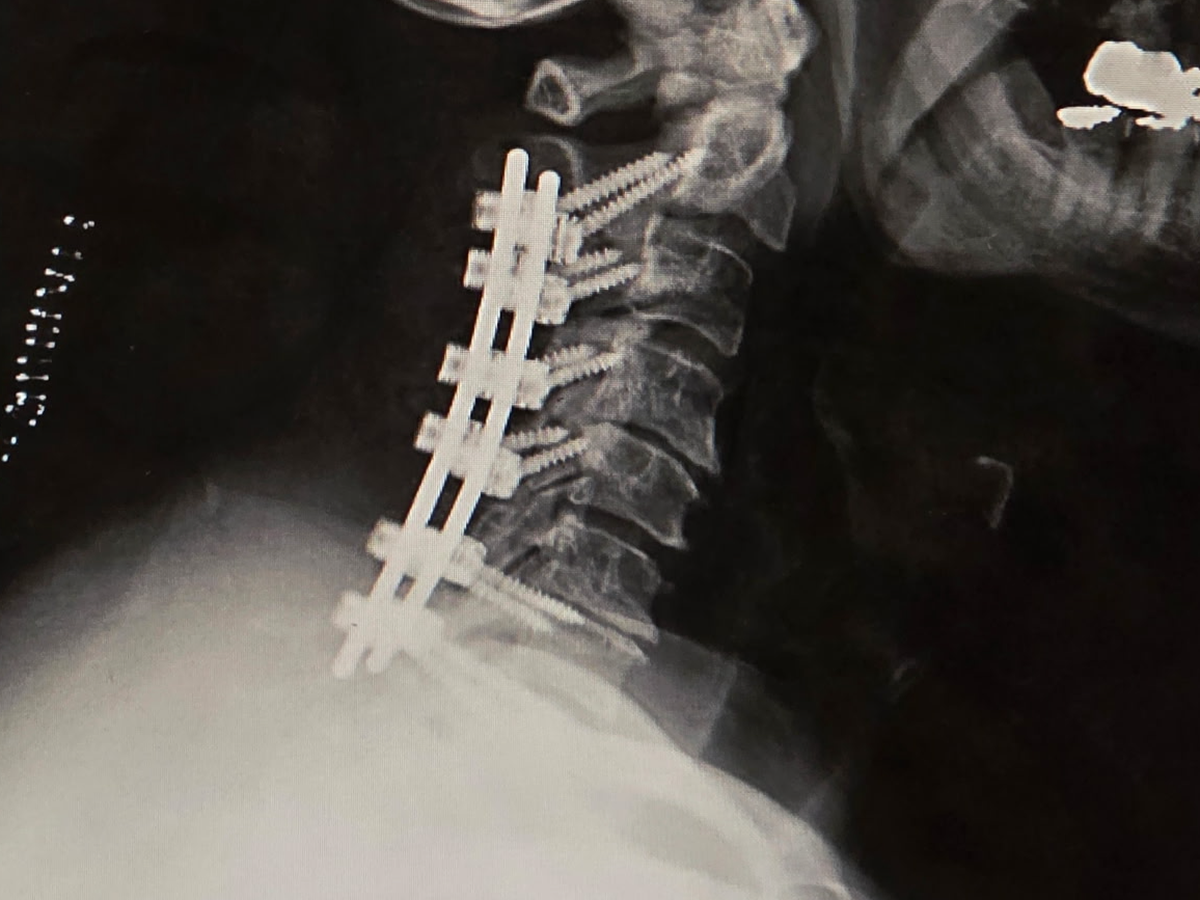

I'm embarrassed to be on here or be doing this, but I don't want to file bankruptcy and I don't want to lose everything I have and built. I had neck surgery on August 11th, and I ended up with C5, C7 & C8 Palsy from the operation. I lost total use of my left arm at the time. I've been going to therapy & working on my arm at home. While I am slowly gaining use of my arm, I've come across other medical issues. I was in the ER the other day for more blood clots in my right leg, and my lower back has gotten worse with SEVERE pain. I just had a recent MRI that confirmed that. Unfortunately, I can't do anything with my lower back until the blood clots are resolved, nor can I return to work because I don't have the strength in my left arm. Being self-employed, I don't have any means of income or disability. Like I said, I'm embarrassed to be doing this but not sure what else to do. If you donate, I thank you; if you share this, I thank you. Sincerely, Tom